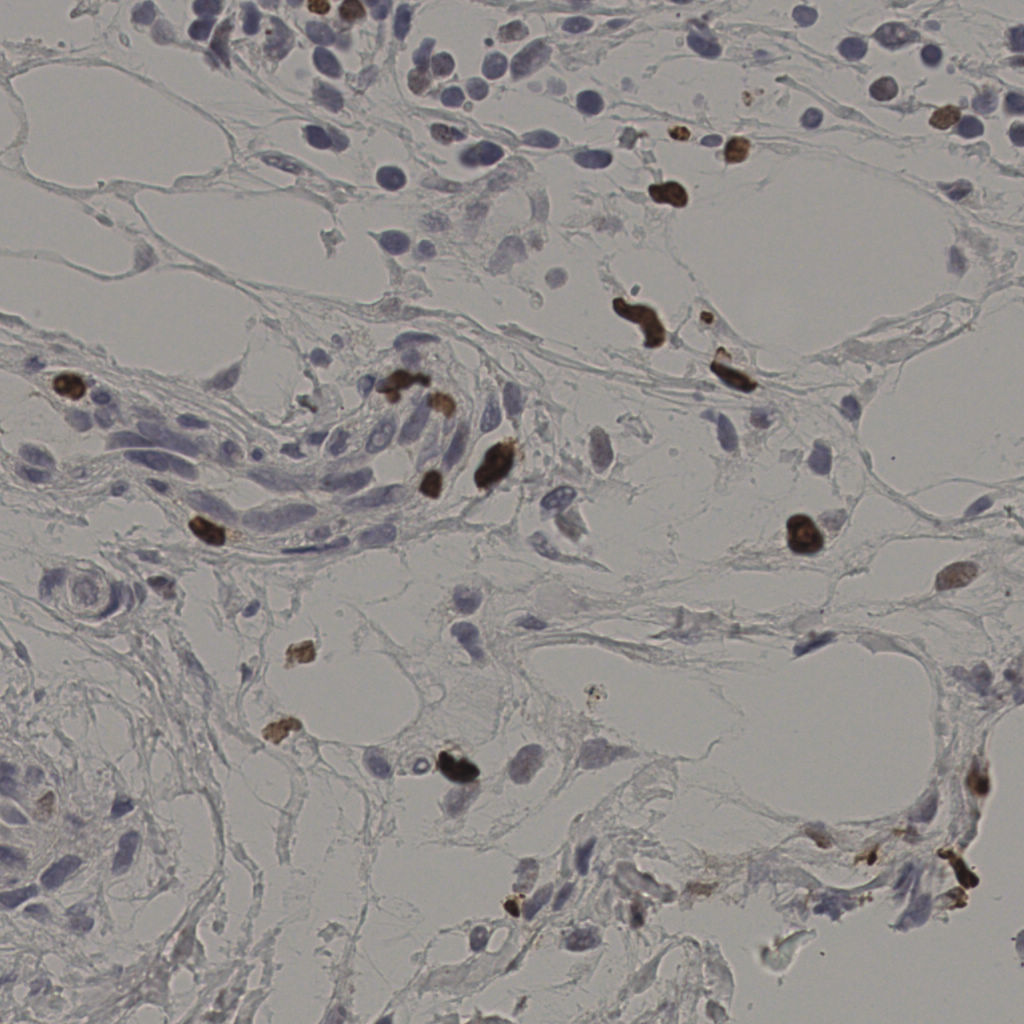

17.75%

Ki67 指数

阴 7986

阳 1723

缩略图

标记后

标记前